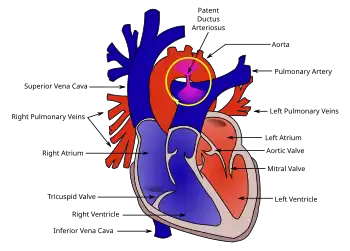

In a normal heart there are four chambers. These are the right and left atria, and right and left ventricles. The right atrium and right ventricle function to pump blood to the lungs while the left atrium and left ventricle pump blood to the rest of the body. There are heart valves in place that inhibit back-flow between these chambers.[4]

An atrioventricular canal defect is developed because of the improper formation of the endocardial cushions, and their job is to separate the different parts of the heart during development when they fuse. It is strongly associated with Down's syndrome. The structures that develop from the fusion of the endocardial cushions are:

- The interatrial septum divides the left and right atrium

- The interventricular septum divides the left and right ventricles.

- The mitral valve and tricuspid valve are formed by the proper division of an early common valve being separated into two.[5]

Atrioventricular canal defect may be divided into partial or complete forms. In the partial form, openings between the left and right atria and improper formation of the mitral valve exist. In the complete form, there is free movement in all chambers because there is a large hole where the atria and ventricles meet, and instead of there being two valves there is one common valve.[4]